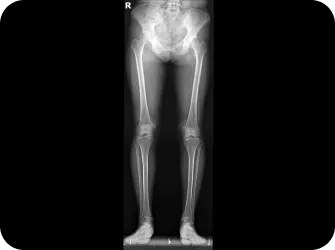

• 다리 길이에 차이가 있다.

똑바로 누운 상태에서 양쪽 다리 길이를 잽니다.

(다리를 일부러 비뚤게 놓거나 자세가 나쁘면 정확한 측정이 곤란)

한 쪽 다리가 짧다면 골반이 비뚤어졌거나 척추가 불안정한 상태입니다.